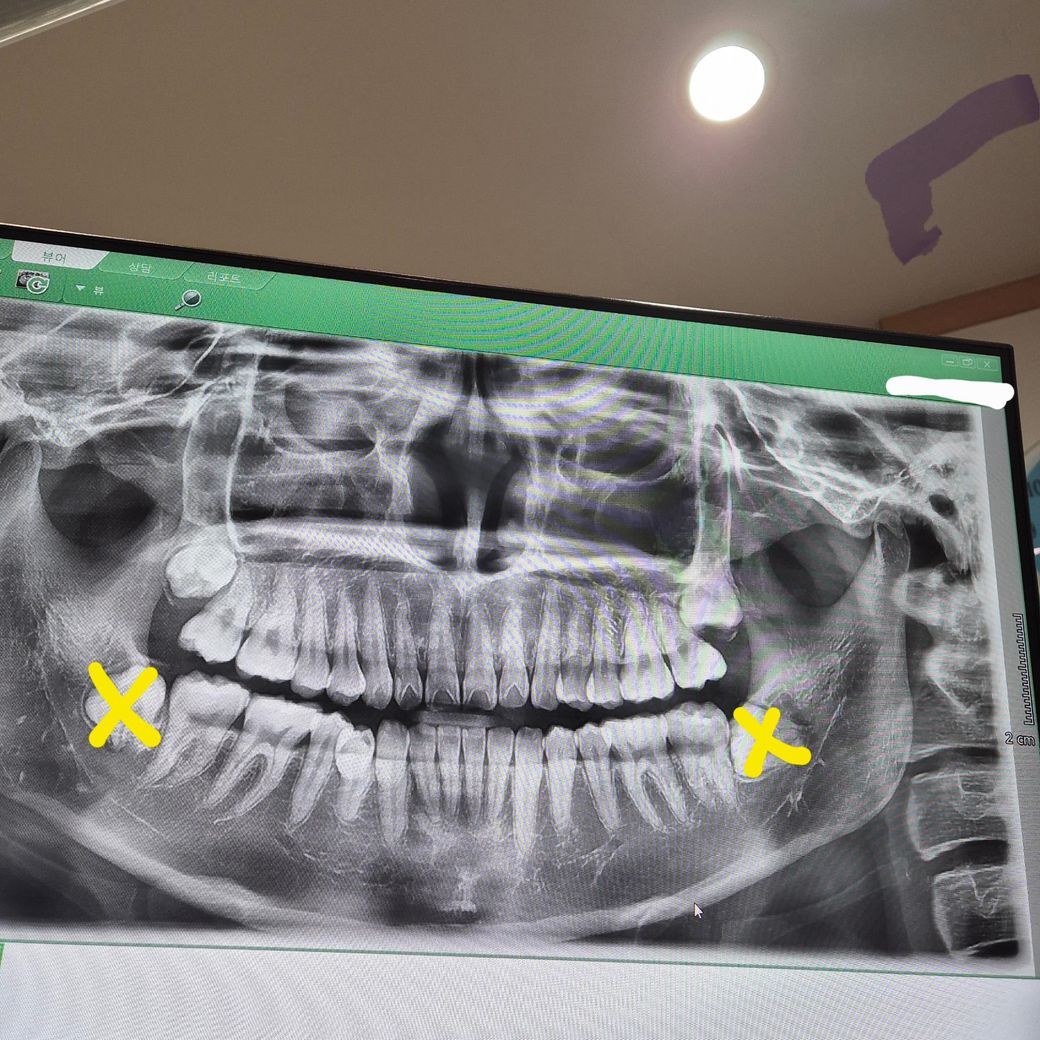

노란색으로 표시한 아래 사랑니는 다 뺀 상태입니다

근데 윗니 사랑니를 빼야할지 고민입니다...

제 엑스레이 사진 보시고 객관적인 평가해주시면 감사하겠습니다! 참고로 현재 제 나이는 만24세입니다.. (한 살이라도 어릴 때 빼야한다고 하셔서 겁먹은상태....)

방사선 사진으로 봤을 경우 사랑니는 치조골 안에 매복되어 있고 특별한 문제가 없어 보입니다.

해당부위에 불편감이 없다면 굳이 발치를 할 필요는 없을 것으로 생각됩니다.